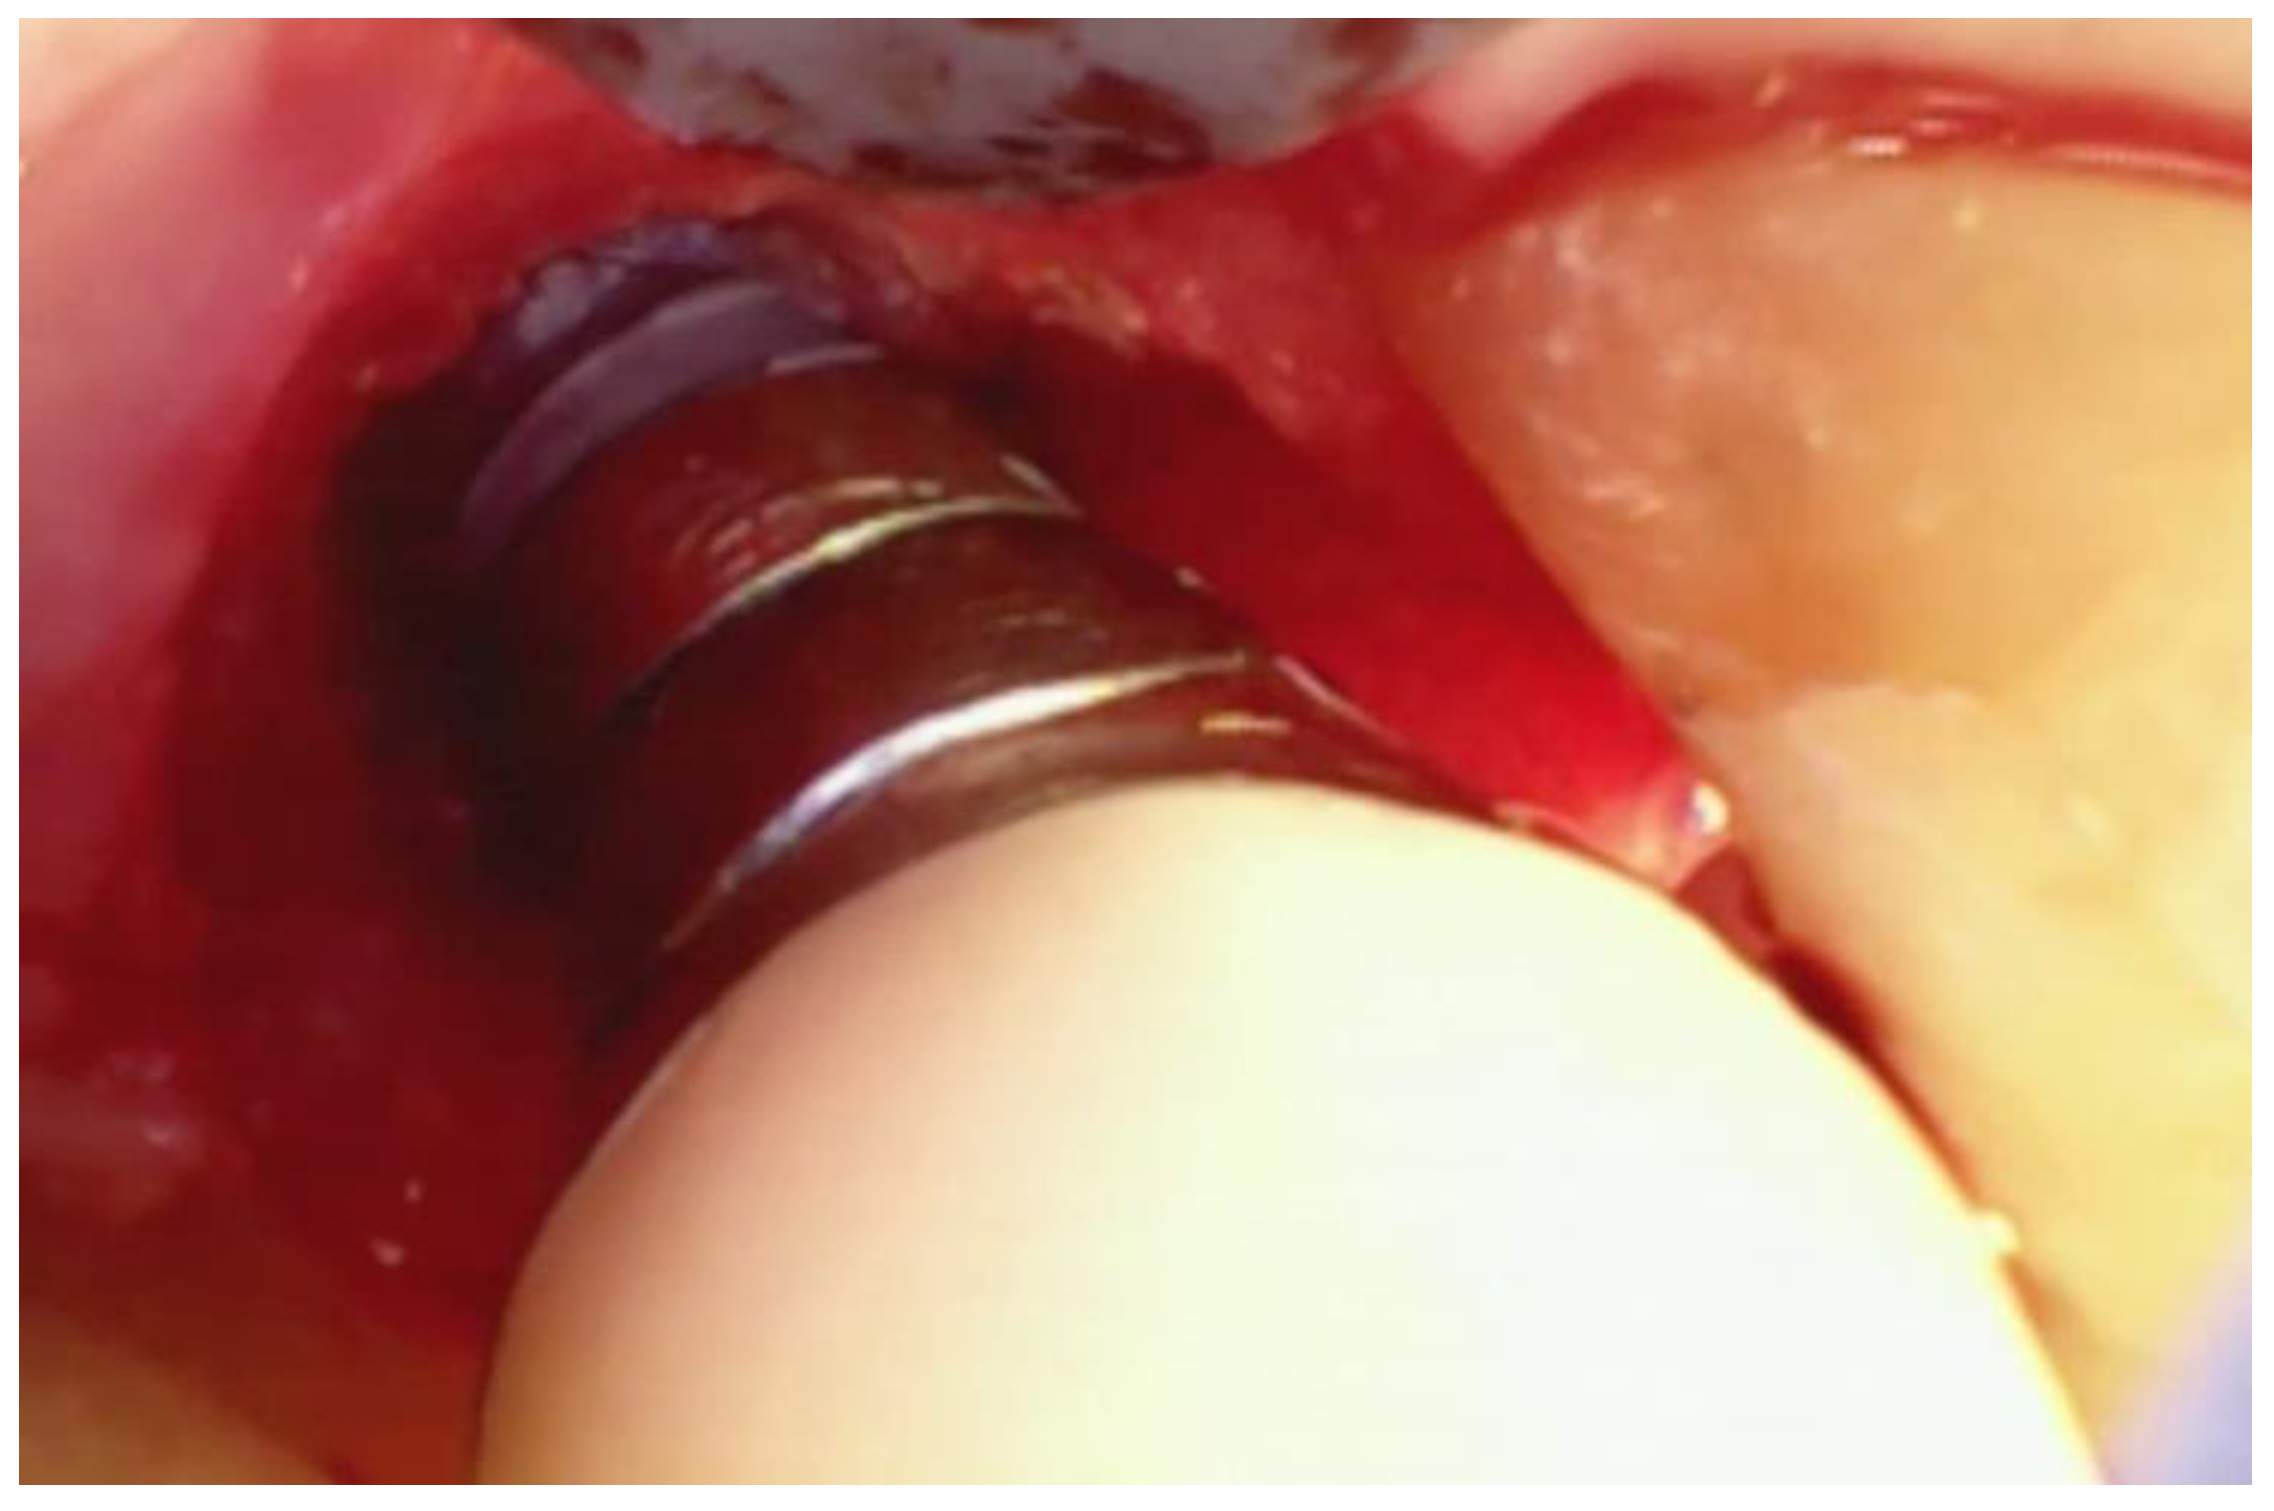

The incisions used are very similar to those previously described for VMIS around natural teeth. A sulcular incision is made around the implant in the area of bone loss. No soft tissue is removed at this point. The incision is extended apically to the level of remaining bone. A split-thickness incision is then made across the base of the adjoining papilla extending to the line angle of the adjacent teeth. As with natural teeth, the split-thickness incision is extended apically for an adequate distance to allow for the insertion of the retractor tip on the videoscope and to allow adequate visualization of the bone loss. (Figure 6).

Figure 6. The tip of the retractor on the videoscope is rotated to an optimal angle and used to gently push back the lingual flap to allow visualization of the bone loss.